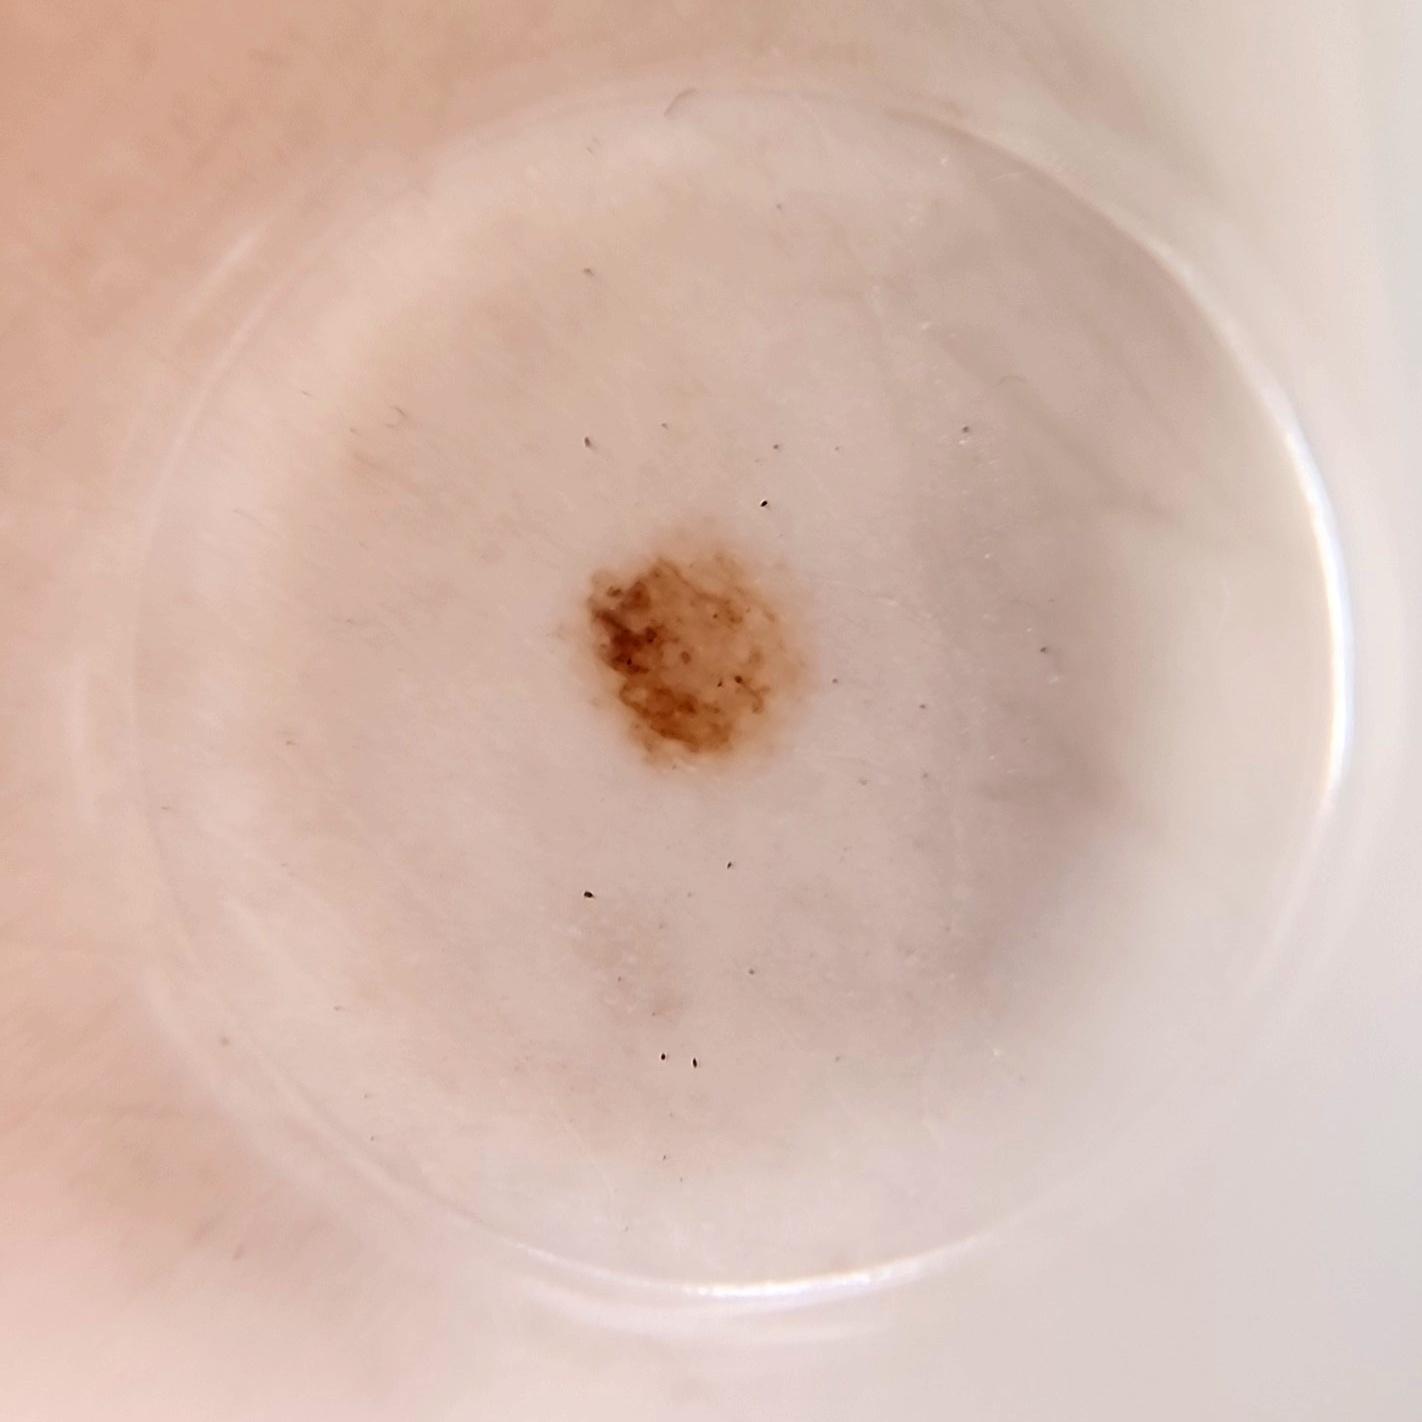

ISIC_8286416

IP_8159579

IL_3192179

acquisition_day 225

age_approx 50

anatom_site_1 Lower extremity

anatom_site_general lower extremity

diagnosis_1 Benign

diagnosis_confirm_type single image expert consensus

image_type dermoscopic

lesion_id IL_3192179

patient_id IP_8159579

sex female